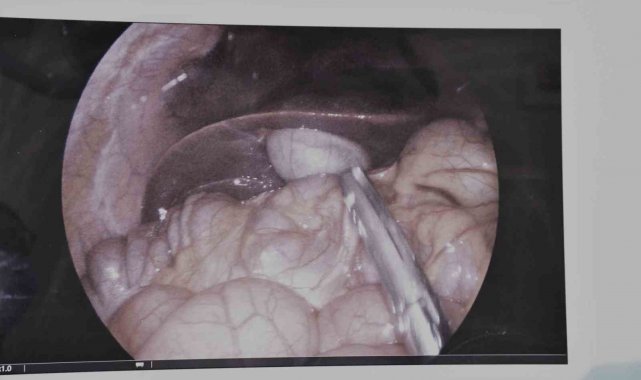

Sık sık tekrarlayan safra kesesi iltihaplanması (kolesistit) şikayeti bulunan 17 yaşındaki bir hasta, hastanede çocuk yaş grubunda ilk kez gerçekleştirilen laparoskopik kolesistektomi ameliyatı ile sağlığına kavuştu.

Operasyonu gerçekleştiren Çocuk Cerrahisi Uzmanı Op. Dr. Serkan Odabaşı, yaptığı açıklamada, hastanın uzun süredir karın ağrısı, mide bulantısı ve sindirim problemleri şikayetleri olduğunu belirtti. Dr. Odabaşı, yapılan detaylı tetkikler sonucunda safra kesesinde enfeksiyon tespit edildiğini ifade ederken, "Bu durumda en uygun tedavi yöntemi, safra kesesinin alınması yani kolesistektomi ameliyatıdır. Operasyonu kapalı (laparoskopik) yöntemle gerçekleştirdik. Laparoskopik cerrahi, karında büyük kesiler açmadan, küçük delikler aracılığıyla özel cerrahi aletlerle yapılan modern bir tekniktir. Bu sayede hastamızın ameliyatı başarılı bir şekilde tamamlandı. Hastamızın kısa sürede taburcu edilmesi planlanmaktadır" dedi.